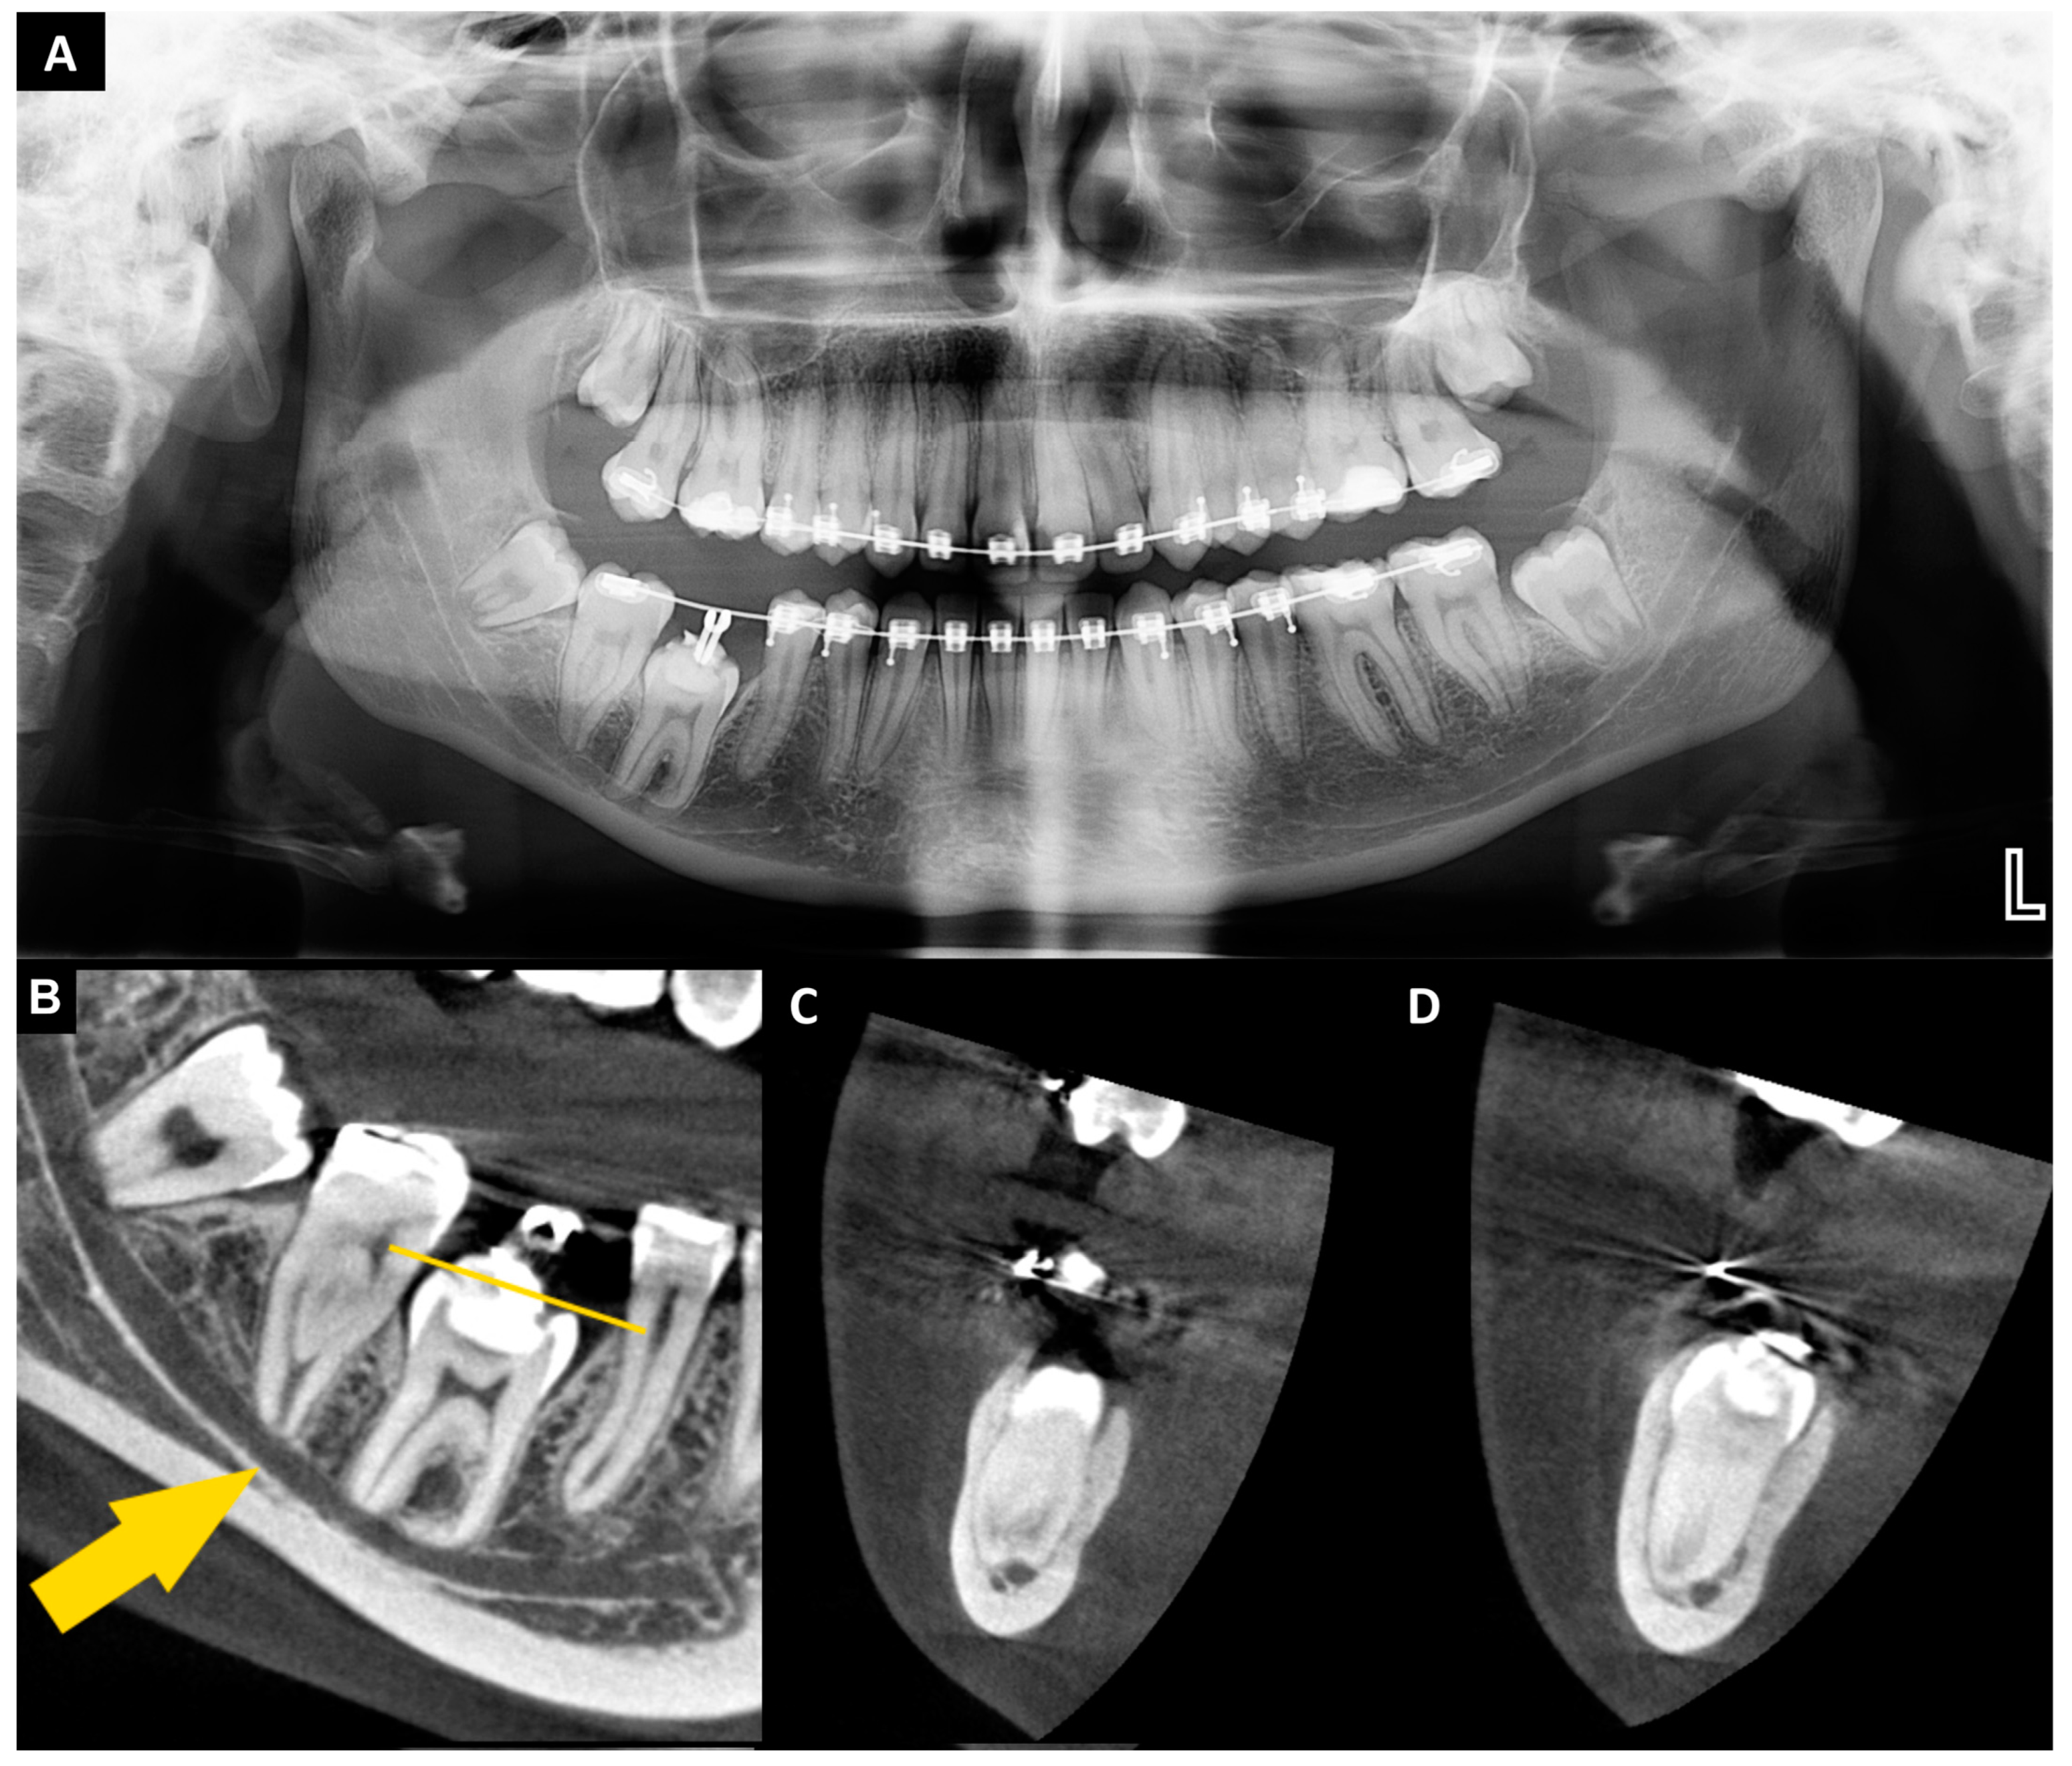

2. Case Presentation